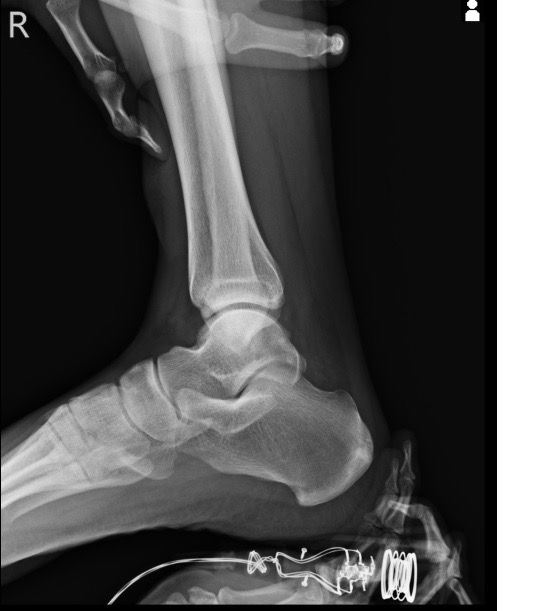

복숭아뼈 미세골절 초음파 사진 관련 질문

발목 접지른 후 치료받는 중인데요 복숭아뼈 미세골절이라고 하셨네요 3월 1일 다친뒤네 3월7일 병원방문후에 위에 초음파랑 엑스레이 촬영했고요 그뒤 반깁스 중입니다. 위에 엑스레이 상에선 안나오는데 초음파 사진에선 미세골절이 맞을까요? 골절이 경미한 수준인지 아니면 중한 건지 궁금합니다 그리고 다음주에 병원 방문 후 초음파 또 촬영하기로 했는데 그때 반깁스도 풀 수 있을까요??

발목의 복숭아뼈에 미세골절이 의심되는 경우, 엑스레이에서는 미세골절이 잘 보이지 않을 수 있습니다. 엑스레이는 큰 골절을 잘 확인하지만, 미세한 골절이나 염증 반응은 잘 나타나지 않기 때문이죠. 초음파는 조직의 변화를 보다 민감하게 감지할 수 있기 때문에, 미세골절을 발견하는 데 도움을 줄 수 있습니다. 초음파에서 미세골절이 확인되었다면, 이는 경미한 골절일 가능성이 높아요. 하지만 골절의 정확한 상태나 치유 과정을 판단하려면 정밀 검사가 필요하죠